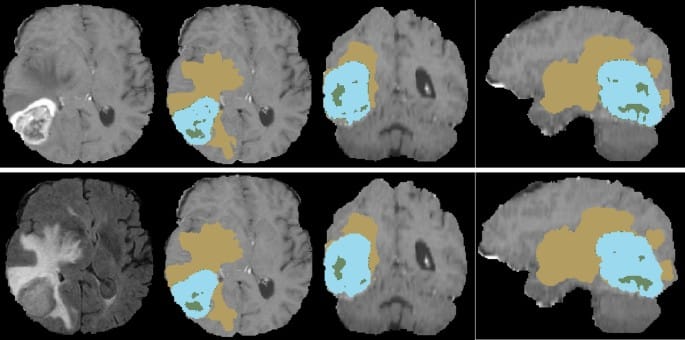

Ontol 3D

CT/MRI 장기 및 병변 자동 분할 및 계측 딥러닝 모델

CT, MRI의 전,후처리 기술과 딥러닝 모델을 통해 전신 장기 영역과 다양한 병변을 분할하고 계측합니다. 영상 정합을 통한 시계열 병변 추적과 분석이 가능합니다.

- 뇌 MRI 영역 분할

- 뇌 주요 영역 분할(Segmentation & Parcellation)

- 뇌종양(Glioma)